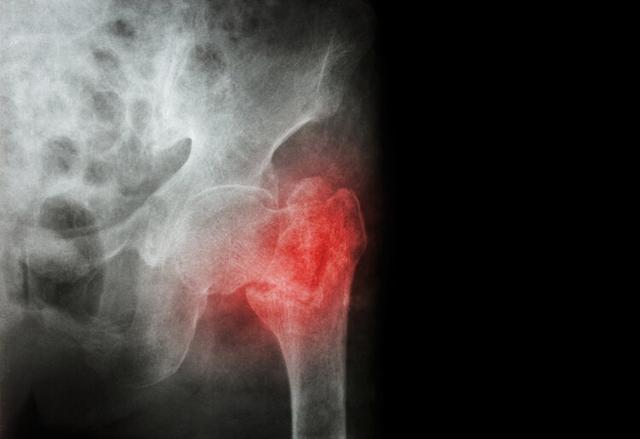

骨肉瘤是一种起源于间质细胞的原发恶性骨肿瘤,多发生于儿童和青少年,主要侵蚀长骨以及骨盆、脊柱、下颚等部位,发病率为百万分之三,每年我国有近1万人被它“盯上”。

骨肉瘤的诊治包括临床、影像、病理三科联合诊断,其分类和诊断极为复杂,单纯依靠X线,术前的诊断和病期评估不准确,近年来影像学诊断的发展,如超声、CT、MRI、核素扫描、PET—CT等检查对术前的诊断和病期评估有了很大的帮助。另外,穿刺针活检是绝大部分骨肉瘤诊断的必要途径。